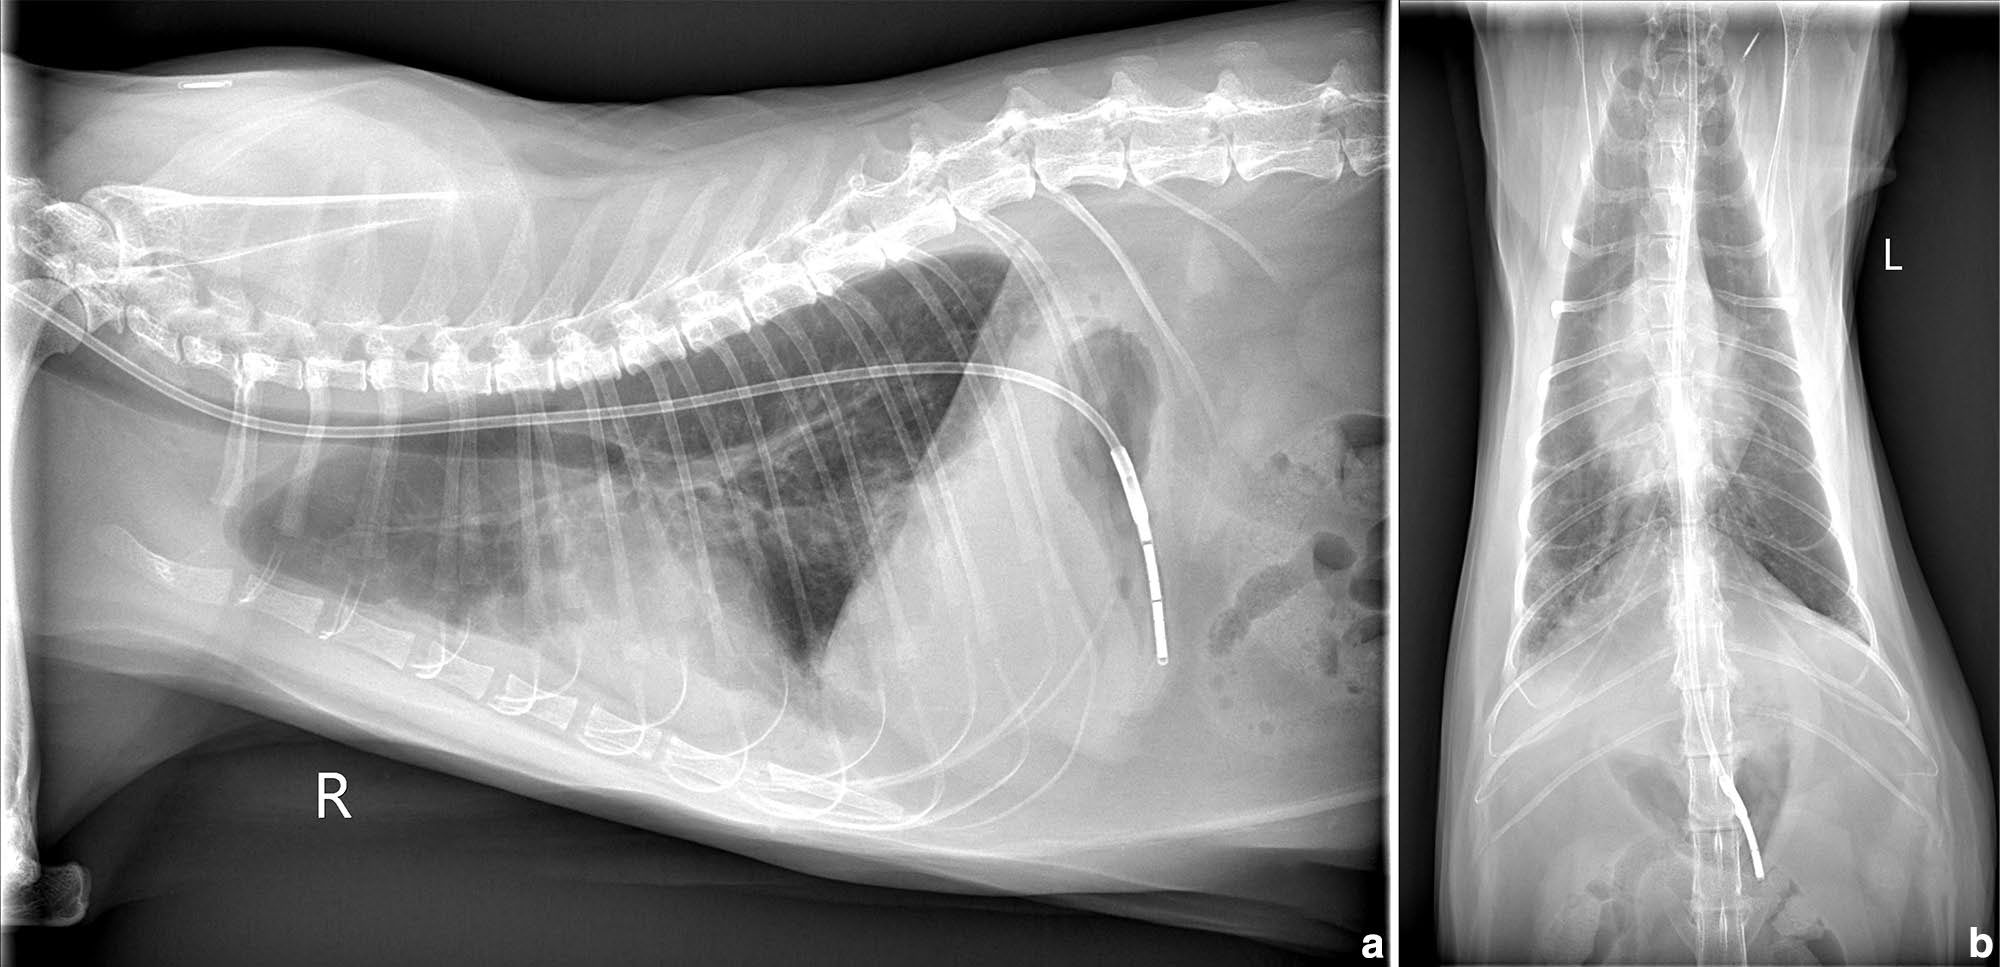

体重5.9 kg。精神沉郁,呼吸急促(100次/分),高热(41.2°C)。胸部X线呈混合性肺征,间质、支气管及肺泡均受累,后叶最严重(图1)。轻度胸腔积液与心脏增大,提示心肺疾病。

图1. 胸部X线片(a)侧位:弥漫混合性肺征,间质、支气管及肺泡病变以后叶最显著,伴轻度胸腔积液及中度心脏影增大。(b)背腹位:更清楚显示胸腔积液及肺、心细节。